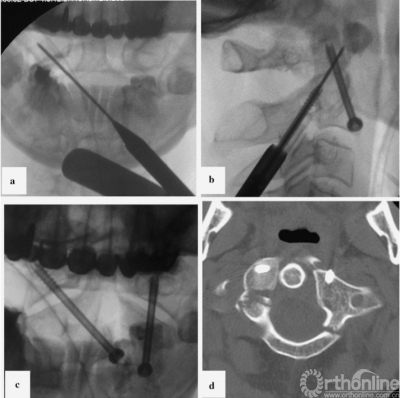

在双平面x线引导下,将K-wire穿过C2椎体下边缘并插入寰椎对侧侧块(图3a),并用其钻通骨隧道。在骨隧道中插如一根空心皮质内固定螺钉(直径4mm,长度38mm),螺钉头在C2椎体的位置有利于左侧关节的Reindl固定。然而,C2双侧侧块明显变薄(CT数据;图1,右)使得我们无法实施这种方法。

在使用Halo架的同时,将患者翻身至俯卧位,采用标准技术用直径4mm、长度40mm的空心皮质内固定螺钉进行左侧单侧经关节固定[7](图3 b)。x线图像及CT对照数据见图3c,d。在术后拆除Halo架。

图3病例1:固定时x线及对照CT扫描;a、使用对侧轨迹将克氏针置入右侧侧块;b、左侧单侧后路经关节固定;c、开口位x线;d、置钉后的三维CT扫描图片(轴位);螺钉位于寰椎两侧的侧块,左侧为双皮质;CT,计算机断层扫描

First, we used the Halo device for head fixation whilst the patient was in the supine position. One of the Halo pins was placed according to the location of the skull fracture and skin wound. For this reason, we fixed the Halo using only three pins, which allowed us to reposition appropriately and achieve immobilization during surgery. Reduction of the vertical atlantoaxial dislocation was performed using traction. Skin incision for contralateral screw insertion was planned using transoral radiography. A K-wire was attached according to the screw insertion trajectory. The intersection between the K-wire line and the medial edge of the sternocleidomastoid muscle indicated the midpoint of skin incision. The left anterior bar of the Halo device was temporally removed to facilitate approach performance during contralateral fixation. The left transcervical approach to the base of the C2 vertebra was performed through a 2cm skin incision. A port for the cannulated instrument was placed near the lower edge of C2, 5mm lateral from the midline. K-wire was inserted through the lower edge of C2 into the opposite lateral mass of the atlas under two-plane X-ray control (Fig.3a). This K-wire was used for bone tunnel drilling. A cannulated self-tapping cortical lag screw (4mm in diameter and 38mm in length) was inserted through this tunnel. The position of the screw head in the C2 vertebra facilitated fixation of the left lateral joint using the Reindl method; however, significant, bilateral thinning of the anterior lip of the C2 lateral mass (CT data; Fig.1,right) prevented us from using this technique. While using the Halo device, the patient was subsequently turned over into the prone position, and a left-sided unilateral transarticular fixation using a cannulated self tapping cortical lag screw (4mm in diameter and 40mm in length) was performed using the standard technique[7] (Fig.3b). Control X-ray images and CT data are provided in Fig.3c, d. Following surgery, the Halo device was removed.

Fig. 3 Case 1: X-ray images of the fixation stages and control CT scan. a K-wire insertion into the right lateral mass using a contralateral trajectory. b Left-sided unilateral posterior transarticular fixation. c Control X-ray in the transoral plane. d CT scan control after screw insertion (axial plane). Screws are located in the lateral masses of the atlas on both sides and are bicortical on the left side. CT computed tomography